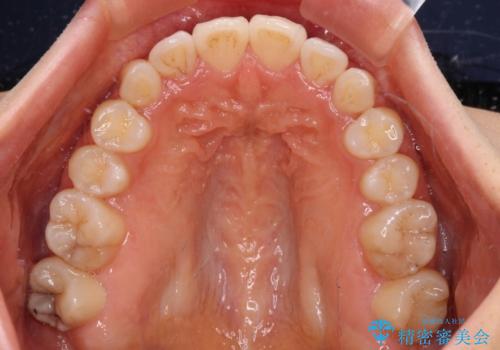

カリエールディスタライザーを併用したことで、確実かつ短期間で治療を終えることができました。

- 飛び出した前歯と口元の突出感を気にして来院された患者様です。

奥歯の咬み合わせを見ると、上顎が下顎に対して相対的に前方にありました。

口元の突出感を改善するためには、上顎臼歯を後方に移動させた咬み合わせにする必要があります。

インビザライン単体で改善することも可能ですが、達成する可能性が高くないため、カリエールディスタライザーという補助装置を併用して、より確実性を上げることとしました。

奥歯の咬み合わせを改善しながら、並行してインビザラインで歯列を整えることとしました。